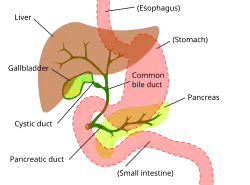

Das Gallengangskarzinom kann in jedem Abschnitt des Gallengangsystems auftreten. Tumoren, die in den innerhalb der Leber liegenden Gallengängen wachsen, heißen „intrahepatisch“ (Hepar = Leber), und Tumoren, die im Gallengangsystem außerhalb der Leber auftreten, werden „extrahepatisch“ genannt. Tumoren, die an der Ausgangsstelle des Gallengangsystems auftreten, heißen „perihilär“, und solche, die an der Vereinigungsstelle der beiden aus der Leber austretenden Gallengänge liegen, werden als Klatskintumoren[27] bezeichnet, wobei die Klatskintumoren heute den perihilären Tumoren zugerechnet werden. Obwohl das Gallengangskarzinom bekanntermaßen ein Tumor der epithelialen Zellen der Gallengänge ist, blieb bislang unbekannt, aus welchen Zellen sich der Tumor entwickelt. Man vermutet, dass er aus einer pluripotenten Stammzelle der Leber herrührt.[28][29][30]

Vermutlich durchläuft das Gallengangskarzinom – ähnlich wie der Dickdarmkrebs – eine Serie von Entwicklungsschritten von Hypoplasien über Metaplasien und Dysplasien hin zum Karzinom (Adenom-Karzinom-Sequenz).[31] Deshalb spielen Prozesse wie chronische Entzündungen und eine Verengung der Gallenwege, die mit einer Flussbehinderung der Gallenflüssigkeit einhergehen, bei der Entwicklung dieses Tumors eine Rolle.[31][32][33] Das histologische Bild des Gallengangskarzinoms kann von undifferenziertem bis hin zu gut differenziertem Gewebe variieren. Der Tumor ist oft von einem fibrotischen oder desmoplastischen Gewebe umgeben. Im Falle einer ausgeprägten Fibrose kann es schwierig sein, ein gut differenziertes Karzinom der Gallengänge von einem nur reaktiv veränderten Epithel zu unterscheiden. Es gibt keine völlig spezifische immunhistochemische Färbung, die bösartig verändertes von gutartigem Gallengangsgewebe unterscheidet. Markierungen für Cytokeratin, Carcinoembryonales Antigen und Mucine können bei der Diagnose hilfreich sein.[34] Die meisten Tumoren (über 90 %) sind Adenokarzinome.[35]